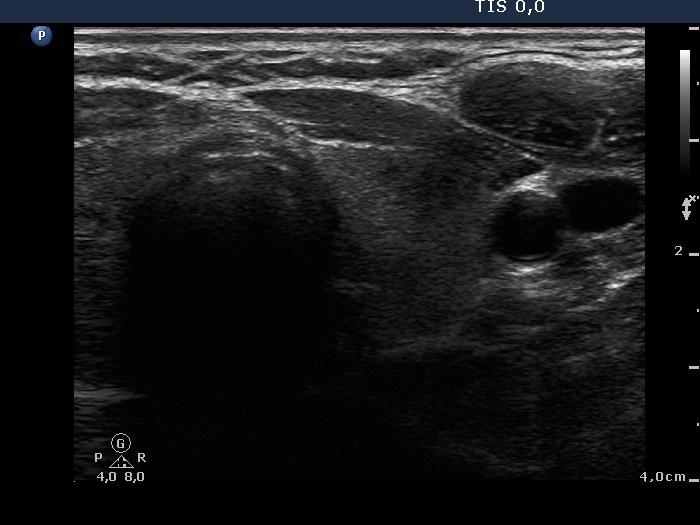

Ultrasonography: There were many hypoechogenic areas with blurred borders within both lobes. The vascularization was decreased.